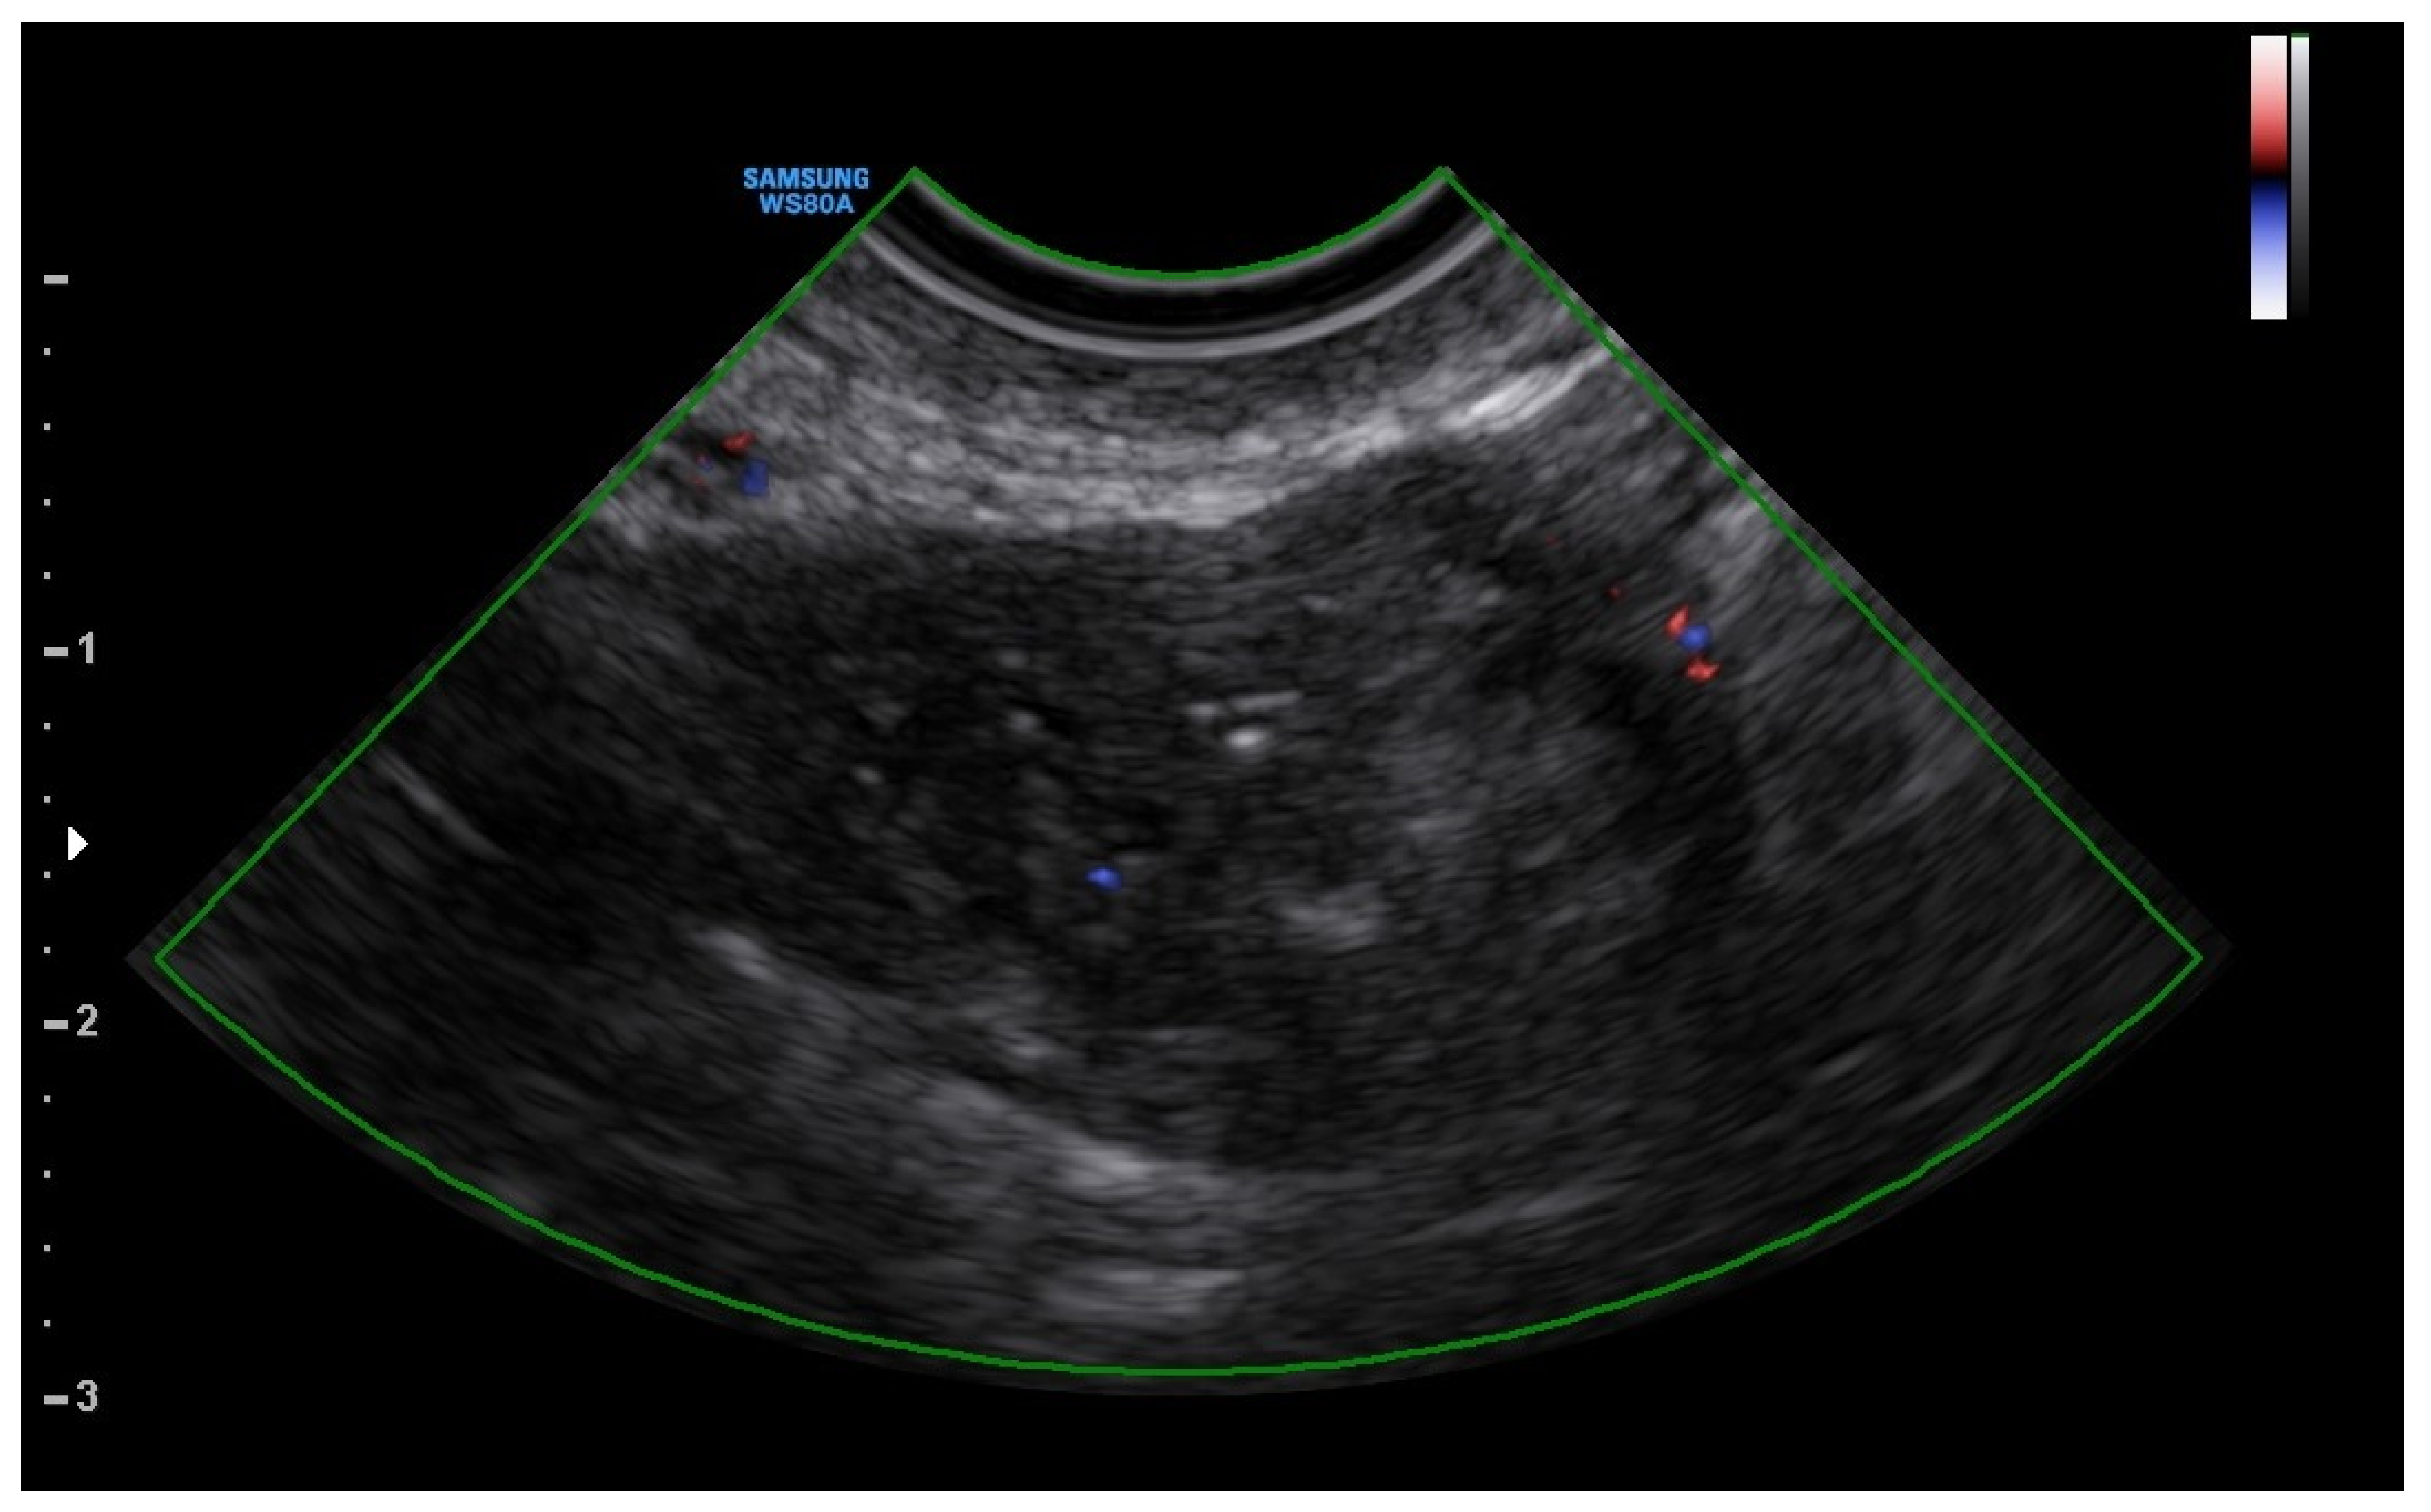

A 25-year-old woman, with a history of left tubal laparoscopic salpingectomy for an ectopic pregnancy, sought medical attention at the hospital’s emergency department after an episode of vaginal bleeding at 5 + 6 weeks of amenorrhea. At Day-1, her β-hCG was 2528 mUI/mL but a transvaginal ultrasound scan (TVUS) showed no clear evidence of pregnancy. Therefore, the patient was admitted with a diagnosis of pregnancy of unknown location (PUL). Upon admission, the patient was clinically and hemodynamically stable and did not report any pain or active bleeding. Serial measurement of her β-hCG in the following days was consistent with a suboptimal growth (3696 at Day-2, 5898 at Day-4, 10,984 at Day-7). Repeated TVUSs failed to show sure evidence of pregnancy until Day-7, when an intramural vascularized mass of 27 × 8 × 20 mm, with a gestational sac of 7 mm, a yolk sac and a 2 mm embryo with a heartbeat, was detected (Figure 1). Pelvic nuclear magnetic resonance (NMR) performed at Day-7 confirmed the presence of an intramyometrial T2-hypointense signal alteration of 20 mm in the right cornual area, surrounded by ectasic vessels, suggestive of interstitial pregnancy (Figure 2). After thorough counselling, a conservative management was proposed and accepted by the patient. The patient was administered a single oral dose of mifepristone 600 mg in combination with multidose systemic MTX 72 mg on days 0, 2, 4 and 6 from diagnosis. Follow-up by TVUS and β-hCG measurement was carried out. By Day-15, β-hCG reached a plateau and started reducing. A TVUS confirmed the termination of the pregnancy by involution of the gestational sac and the presence of the embryo with the disappearance of the fetal heartbeat. After 22 days from treatment, while the pregnancy was disappearing, in the same site, TVUS showed the appearance of a myometrial tubular hypoechoic region of 37 × 38 mm with an intensely vascular and multidirectional flow. Spectral Doppler ultrasound showed a low-resistance, high-velocity (peak systolic velocity of 128 cm/s) flow pattern, suggestive of uterine arteriovenous malformation (AVM) in the location of the previous interstitial pregnancy (Figure 3). The patient remained asymptomatic. To avoid menstrual bleeding and minimize the risk of metrorrhagia, a depot 3.75 mg shot of a GnRH analogue was administered every 28 days for 4 months. Considering the desire to preserve the fertility of the patient, the absence of guidelines for the treatment of AVM and the good results presented in the literature on uterine artery embolization as a conservative treatment, we performed a right uterine artery embolization, with sonographic resolution of the AVM within 3 months (Figure 4). We accessed the right common femoral artery and a 5-Fr introducing an angiographic sheath was placed. A 5-Fr Cobra catheter (Cook, Bloomington, IN, USA) was used to perform nonselective angiograms of the internal iliac arteries in order to achieve a general understanding of the vascular anatomy; the right internal iliac artery was selected after creating a Waltman loop with the Cobra catheter. The right uterine artery was selected using a microcatheter ranging from 2.0 to 2.4 Fr. As embolic materials, polyvinyl alcohol particles were used (Contour; Boston Scientific, Cork, Ireland). The rescue treatment had no complications. We present an unpublished case of interstitial pregnancy in a hemodynamically stable woman at an early gestational age successfully treated with medical therapy using MTX and mifepristone, who developed a peculiar complication.

Figure 4. Resolution of the AVM after 3 months.